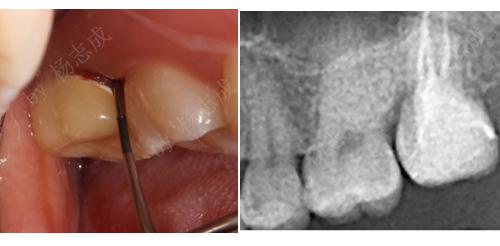

术前

术后